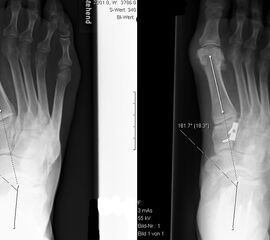

Dorsalflektierende Osteotomien des medialen Mittelfuβes (Abb. 6 – 9, Video 4)

• Erhöhter lateraler Talo-Metatarsale I Winkel (Meary-Winkel) als Ausdruck des plantarflektierten medialen Mittelfuβes, insbesondere im "forefoot driven hindfoot varus" (positiver Coleman block Test).

Generell wird die dorsalflektierende MT I Osteotomie (Abb. 6 und 7) nicht isoliert ausgeführt, sondern ist Teil der gesamten Hohlfuβ-Korrektur. Beim absolut flexiblen Hohlfuβ ist sie gelegentlich zusammen mit einem Peroneus longus auf brevis oder einem Release der Plantarfaszie ausreichend. Diese Osteotomie ist einfach durchzuführen und hat eine geringe Pseudarthroserate.

Eine ähnliche dorsalflektierende Osteotomie des Os cuneiforme mediale (reversed Cotton Osteotomie, Abb. 8 und 9), ebenfalls mit Entnahme eines dorsal basierten Knochenkeils, ist effektiver im Ausmass der Korrektur, jedoch oftmals wegen der Insertion des kräftigen Lisfranc-Ligaments nur schwierig zu schliessen.

• Aufsuchen des Tarsometatarsale-I-Gelenks (TMT-I-Gelenk). 1 bis 1.5 cm distal davon wird die Osteotomie-Ebene mit einem Kirschnerdraht parallel zum TMT-Gelenk markiert.

• Sägen einer subtotalen Osteotomie, wobei der proximale Schnitt parallel MT I Gelenkfläche erfolgen sollte, Basis des Keils 4-6 mm je nach Ausmass der gewünschten Korrektur, konvergierender 2. Sägeschnitt, die plantare Kortex bleibt für mehr Stabilität intakt.

• Evaluation der gewünschten Korrektur mit simulierter, plantigrader Belastung des Vorfuβes: MT I und V Köpfchen sollten auf gleicher Höhe in Relation zur Tibiaachse sein, bei prominenten MT II und III Köpfchen entsprechende dorsalflektierende Osteotomien (Basis des Keils 2 bis 4 mm).

• Fixation der Osteotomie z.B. mit einer 3-Loch 2.0 DCP (exzentrisches Bohren zur Kompression der Osteotomie).